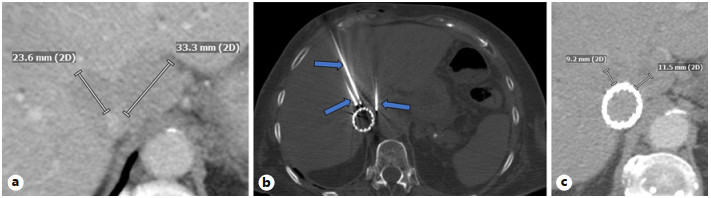

Abstract: Small bowel-origin carcinoid tumor is indolent but may metastasize relentlessly to various sites, including the liver. Over the past 9 years, we have treated a 69-year-old woman who has undergone 5 percutaneous liver ablations, 5 hepatic intra-arterial chemoembolizations, an ovarian cryoablation, and a trans-ventral hernia mesenteric cryoablation. These interventions are all related to her inoperable carcinoid malignancy. After the patient presented with swelling of the abdomen and both lower extremities, computed tomography (CT) angiography was performed, revealing a circumferential hepatic metastatic mass encasing the intrahepatic inferior vena cava (IVC) and extensive third spacing of fluids specific to the IVC distribution below the diaphragm. A venogram of the intrahepatic IVC revealed extrinsic compression causing 95% narrowing of the vessel. A balloon was advanced to the level of the lesion and inflated, increasing the caliber of the vessel. Subsequently, 2 covered aortic stent graft cuffs were deployed in an overlapping fashion within the lumen of the IVC, traversing the area of narrowing. Next, an open-cell aortic dissection stent was placed across both overlapping aortic stents from the renal veins to the hepatic veins. Following this, three 17-gauge cryoablation probes were inserted into the segment 1 intrahepatic lesions encasing the newly stented IVC via an anterior percutaneous approach. Two 10-min freeze cycles were performed with intraoperative CT imaging, demonstrating circumferential coverage of the lesions. Posttreatment venogram revealed patent stent grafts within the intrahepatic IVC, and restoration of vessel patency. No immediate postoperative complications were noted. The patient’s abdominal and lower extremity swelling resolved completely within 1 week after procedure. Two-month follow-up CT demonstrated markedly decreased size of the metastatic lesions and no adverse effects. Six- and 9-month PET-CT scans demonstrated maintained patency of the IVC stent. This palliative procedure allowed the patient to maintain good performance status and alleviated her symptoms of IVC syndrome. The radial force generated by the multiple aortic stents will ostensibly maintain the patency of the intrahepatic IVC. Cryoablation of the encasing metastatic lesion was performed with markedly decreased size of the tumor on the 2-month follow-up.